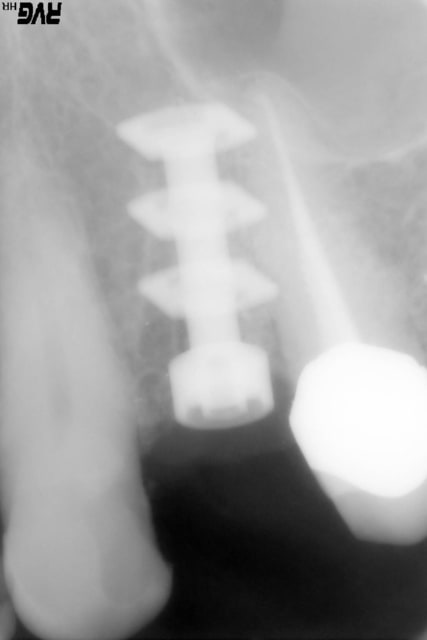

un cas dont j'avais discuté ailleurs avec amibien qui m'avait reproché de ne pas avoir fait la pose en même temps en juin dernier

la pose est de jeudi dernier mon apn est en panne, photo avec le portable, desolé pour le sang mais quand cela saigne il n'y a pas d'échec

il se trouve que j'aimerais utiliser ces photos car c'est le nouveau systeme d'implants, et je n'ai encore pas d'autres cas de fracture en cours

enfin si mais pas aussi belle

j'ai donc agrandi la zone est ce qu'un pro de la photo peut faire mieux?